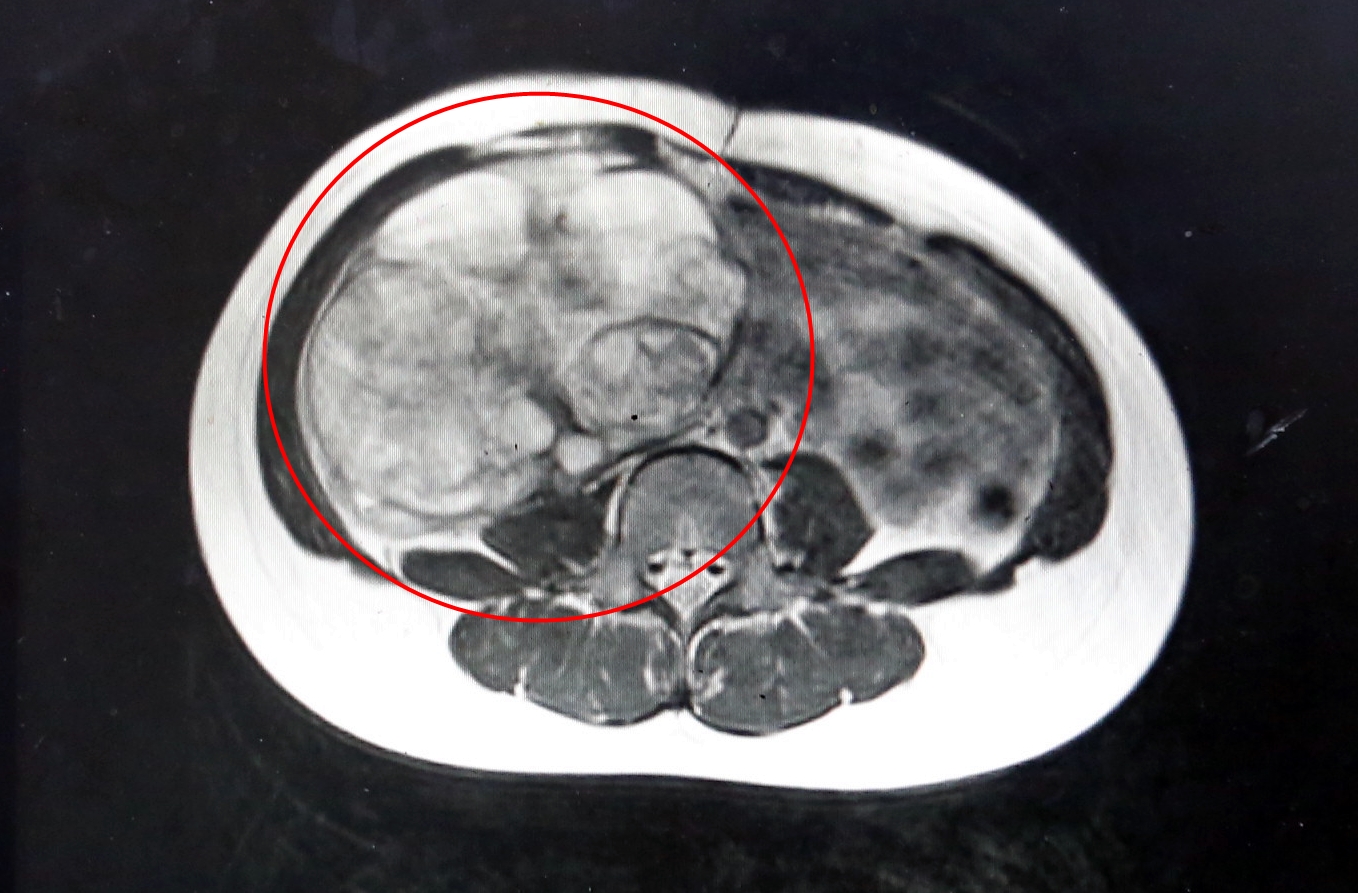

Hình ảnh chụp cắt lớp khối u buồng trứng kích thước lớn ở bé gái 12 tuổi. Ảnh: BVCC.

Các bác sĩ đã tiến hành phẫu thuật cắt bỏ khối u kích thước lớn cho bé gái 12 tuổi. Sau hơn 1 giờ nỗ lực, ca mổ đã diễn ra thành công thuận lợi. Khối u buồng trứng khổng lồ với kích thước 15x20cm, nặng 2kg trong bụng bệnh nhi đã được bóc tách, cắt bỏ trọn vẹn và đưa ra ngoài. Do quá trình xử trí nhanh chóng nên bệnh nhân không bị mất nhiều máu. Sau phẫu thuật, sức khỏe bé gái tiến triển tích cực. Bệnh nhi đã ăn uống bình thường, vận động và đi lại nhẹ nhàng chỉ sau 1 ngày.

Các bác sĩ xác định đây là u quái buồng trứng, có nguồn gốc từ các tế bào mầm biệt hóa với cấu trúc là các loại bã nhờn, xương, tóc, da… Đối tượng dễ bị u buồng trứng đa số là phụ nữ trong độ tuổi sinh sản, từ trên 20 tuổi, ít gặp ở trẻ nhỏ tuổi. U buồng trứng thường là u lành tính, tuy nhiên nếu không phát hiện kịp thời, để u phát triển quá lớn thì có thể gây ra các biến chứng nguy hiểm như: xoắn nang, nhất là đối với các u nang lớn có cuống; vỡ u nang, do u quá lớn kèm xuất huyết bên trong u; ảnh hưởng tới khả năng sinh sản và ung thư hóa…